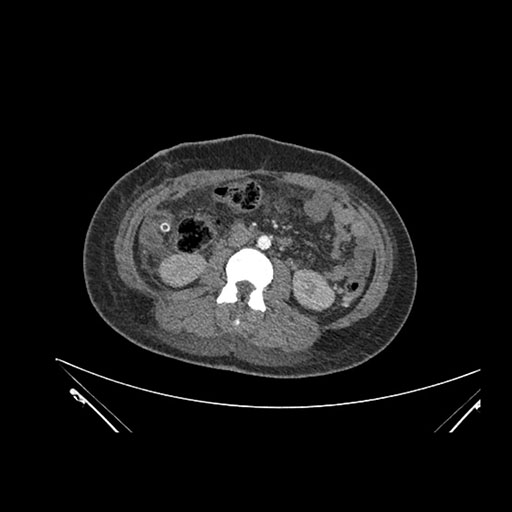

Axial Arterial

Imaging analysis

Based on initial findings, which issue(s) would you be most concerned about?